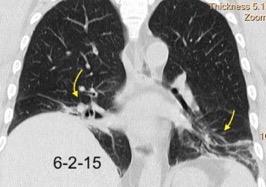

Nódulos pulmonares múltiples. (flechas verdes). Masas paratraqueales. (flechas amarillas). Dudoso ensanchamiento retrocrural (flechas negras). sigue….

Ttawfik A et al. Trans-diaphragmatic Pathologies: Anatomical Background and Spread of Disease on cross-sectional Imaging. Current Problems in Diagnostic Radiology. 2021.

T. mixto de células germinales del testículo

izquierdo Metástasis pulmonares. (flechas verdes). Ganglios paratraqueales. (flechas amarillas). Ganglios retroperitoneales (flechas negras)

Tawfik A et al. Trans-diaphragmatic Pathologies: Anatomical Background and Spread of Disease on cross-sectional Imaging. Current Problems in Diagnostic Radiology. 2021.